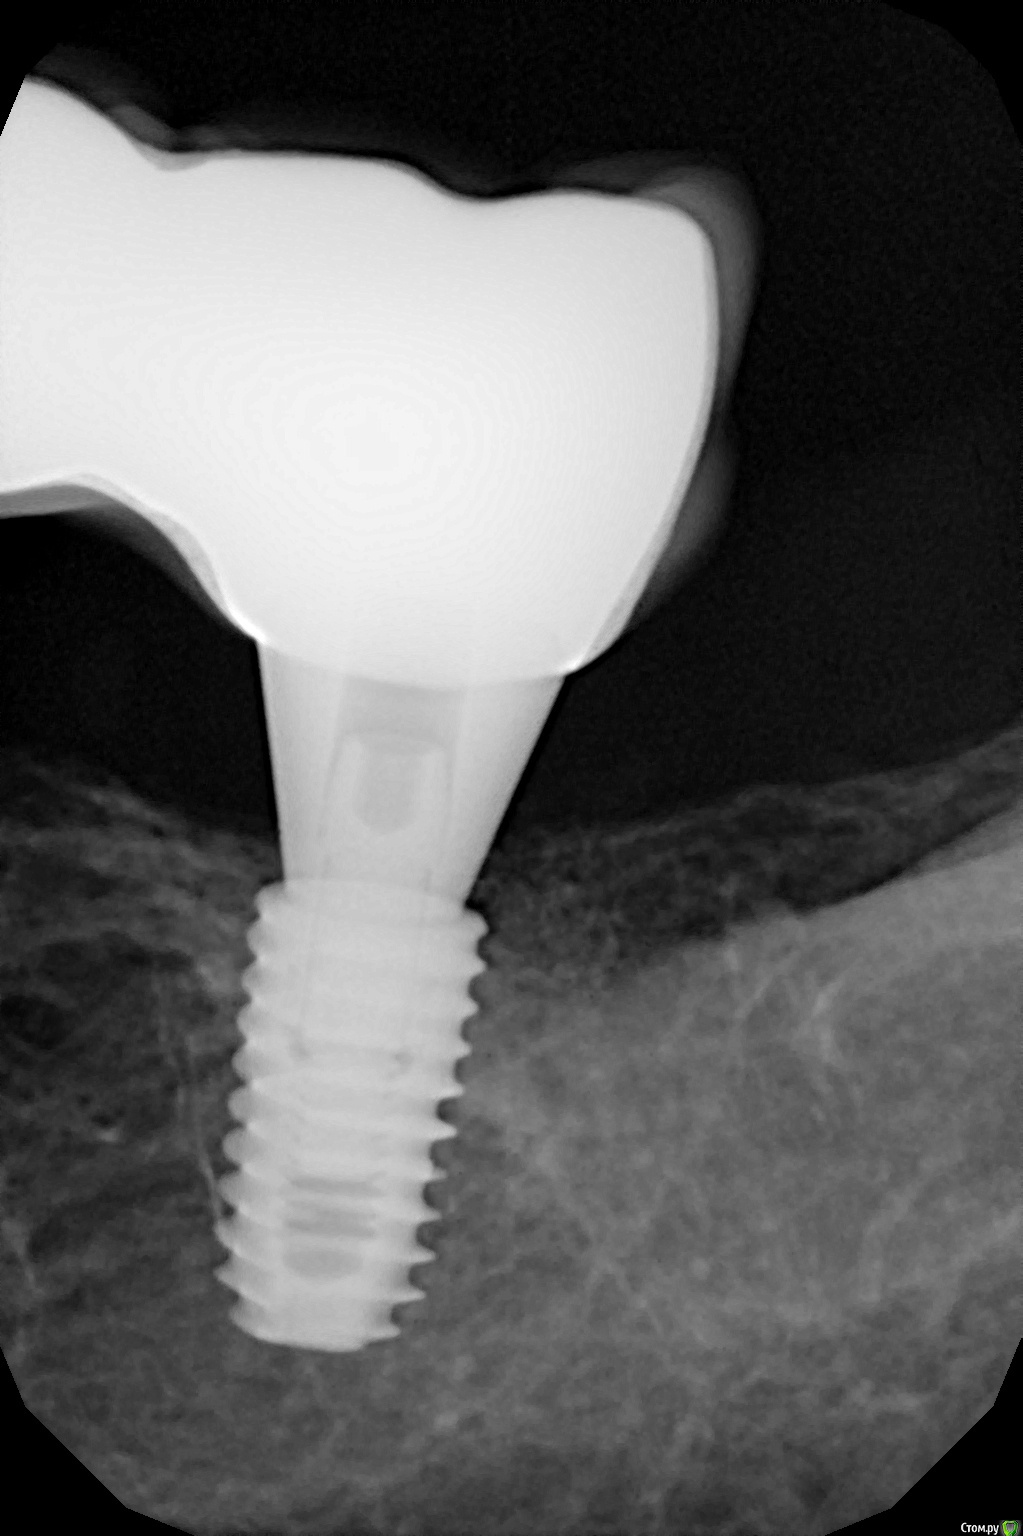

Dman Опубликовано 26 февраля, 2019 Поделиться Опубликовано 26 февраля, 2019 Зачастую это действительно проблема. и для временных коронок тоже нужно снять оттиск. Автору очень рекомендую полистать полный каталог осстема, там есть снимки и описания как и что должно выглядеть. На приложенных снимках трансфер 35 досел, 37 - недосел . Снимок готовой коронки с абатменом, все сидит. Ссылка на комментарий